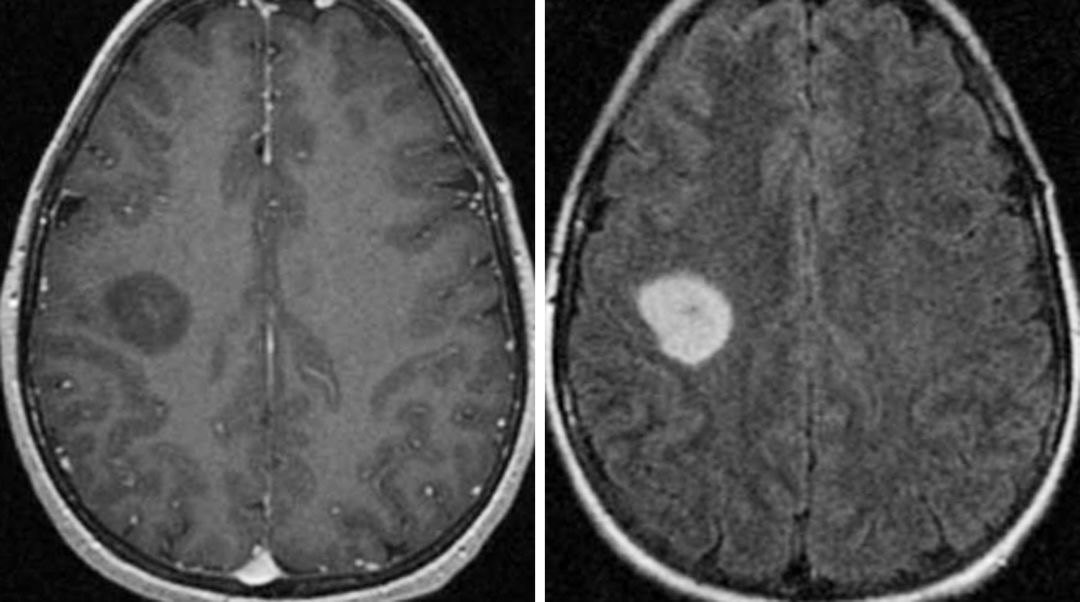

弥漫性星形细胞瘤(ii级)

继荣基础影像~弥漫性星形细胞瘤